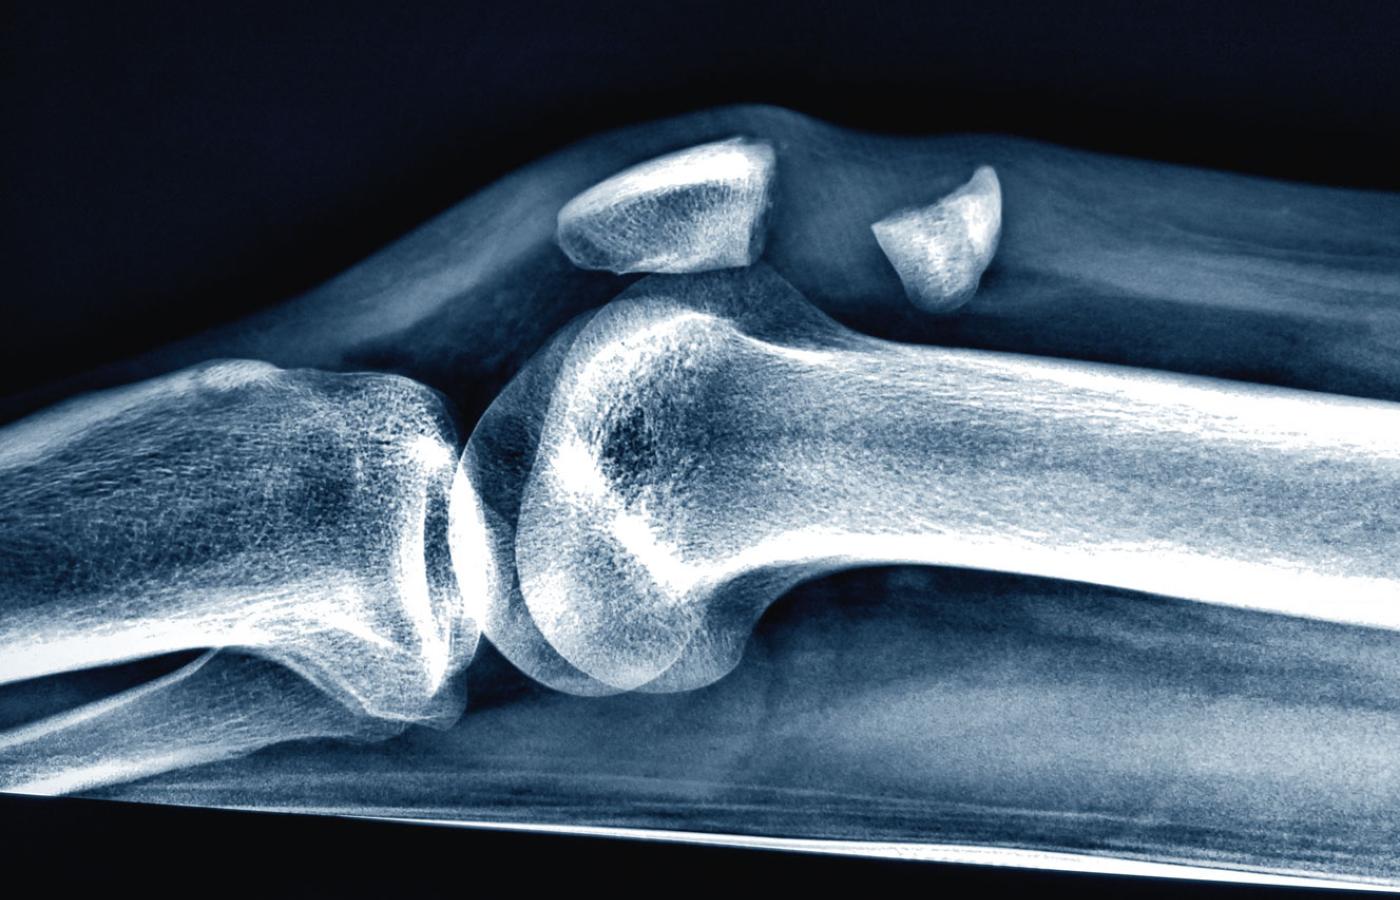

Zwichnięcie stawu kolanowego.materiały prasowe Zwichnięcie stawu kolanowego.